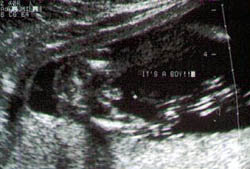

الولد

الأسبوع ال17